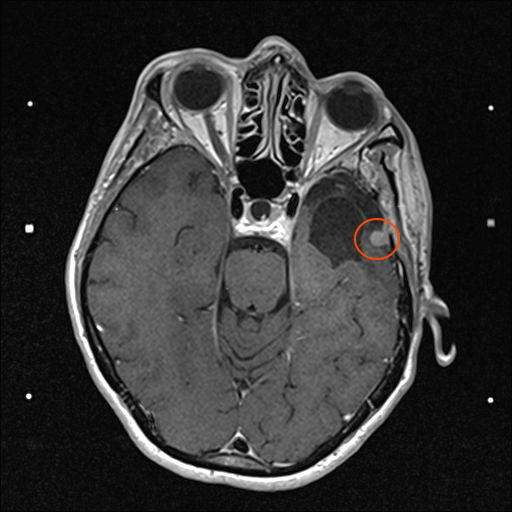

Zu meinem Geburtstag am 27.4. habe ich sehr schöne Geschenke bekommen und kann mich auch über meinen bunten Garten freuen, im Herbst gab es ein Tulpen-Sonderangebot, dem konnte ich nicht wiederstehen! Und nun ist das Ergebnis zu sehen. Am 28. April war wieder mal MRT-Termin. Leider hat es an dem Tag eine Vertretung des auswertenden Arztes gegeben, die Ärztin war super freundlich aber hat keine ganz konkreten Aussagen machen können, aber sie hat mir 2 CDs gebrannt, ich konnte eine gleich bei den Neurochirurgischen Ambulanz abgeben und eine mit nach Hause nehmen. Mein Blick auf die Bilder hat eine nazu unveränderte Lage gezeigt.

Heute war der Termin beim Chirurgen, leider schon um 9:00 Uhr und natürlich wollte ich die knapp 20 km mit dem Rad zurück legen, Stephan wollte gerne mitkommen. Leider war die bereits abgegebenen CD nicht eingelesen worden und so musste erstmal die Datenverarbeitung arbeiten und wir warten, bis wir eine Auskunft bekommen konnten. Fazit: Der bestehende Tumor ist kaum gewachsen. Aber es hat sich leider ein 2. Fund ergeben, sehr klein aber deutlich sichtbar. Aber Maßnahmen sind erstmal nicht notwendig.